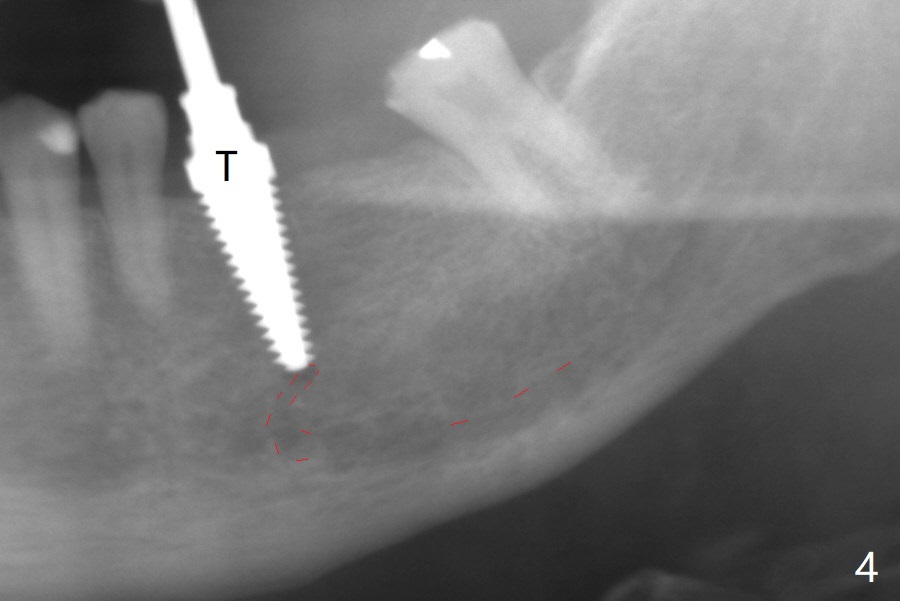

When the tooth #20 is extracted, the buccal and lingual plates are intact, but the apical lesion is deep. A PA is taken (Fig.1). Osteotomy will be established either along the long axis of the original socket (Fig.2 a line) or in the mesial slope (b line). Either osteotomy may damage the Mental Loop (red dashed line). To reduce the complication, osteotomy is being made by inserting 3.8 to 6 mm taps. In fact the 6 mm tap achieves stability (Fig.3,4), but it invades the buccal gap. When the tap is removed, the bottom of the socket is sensitive to probing with oozing from the socket. To reduce further compromise of the buccal space, Lindamann bur is used to remove the bone from the lingual and mesial plate, followed by placing a 6x17 mm implant with >50 Ncm (Fig.5). In fact the implant is placed shallower than the tap. When a 4x17 mm implant is placed at #19, there seems to be clearance from the Inferior Alveolar Canal (Fig.6). Postop there is no paresthesia. The buccal gap is <1 mm, which is filled with Vanilla Graft. After recementing the retainer (crown, C in Fig.7) at #18, periodontal dressing is applied to the sites of #19 and 20. Impression is taken 4 months postop with that of #15.